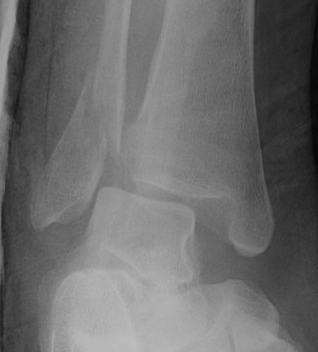

Weber A fibular fracture

Definition

Fracture below level of syndesmosis

Fibular avulsion fracture

Management

Stable

Full weight bear